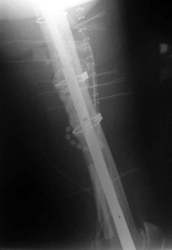

Diese Fraktur ereignete sich 8 Wochen nach Prothesenwechsel. Der Wechsel war bereits problematisch, Frakturen wurden mit Drahtcerclagen befestigt. Es handelte sich jetzt um eine Stückfraktur.